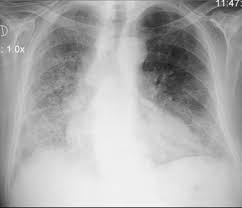

Salud Fibrosis Pulmonar La Enfermedad Que Se Confunde Con El Asma Y Que Es Peligrosa Para Tu Salud

Salud Fibrosis Pulmonar La Enfermedad Que Se Confunde Con El Asma Y Que Es Peligrosa Para Tu Salud from www.ecestaticos.com